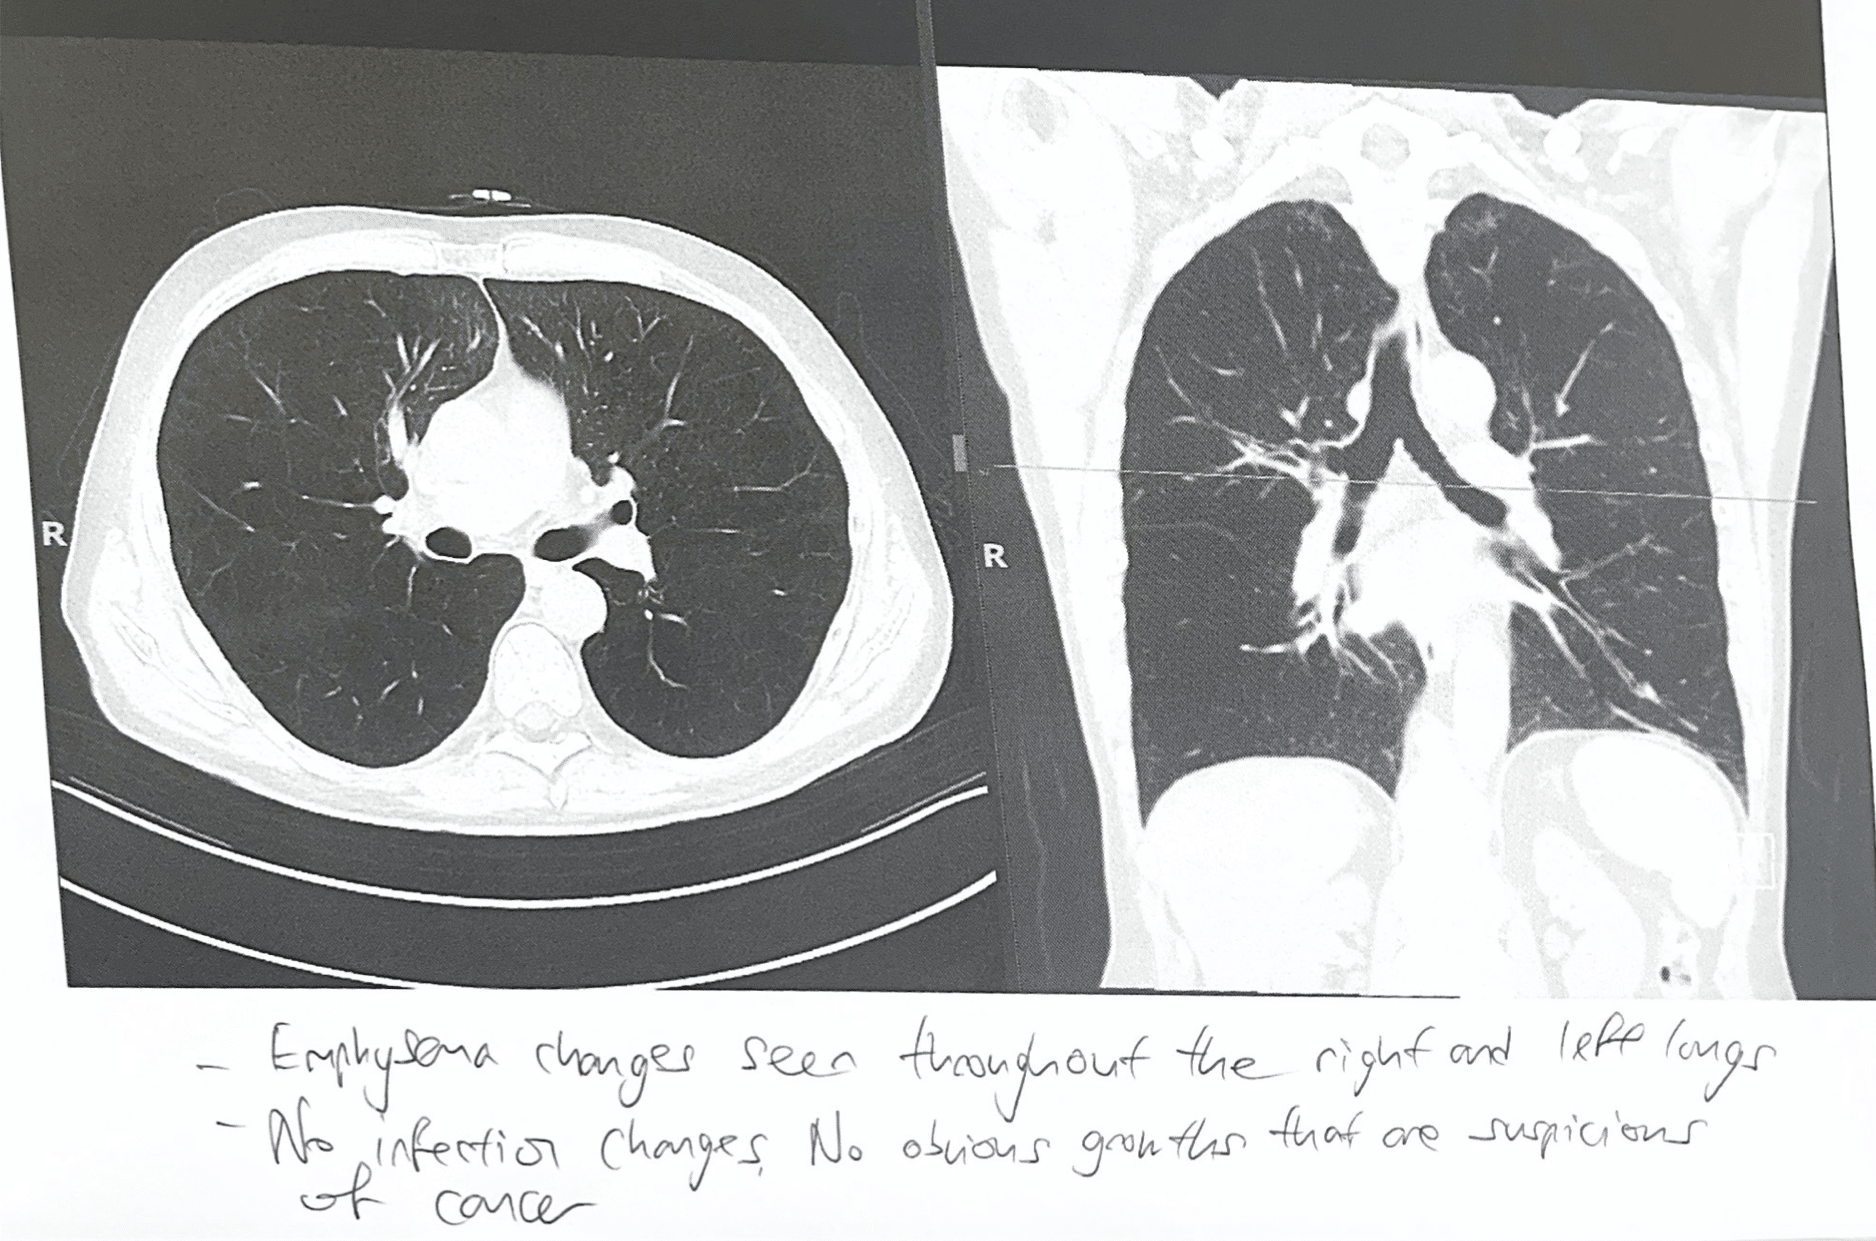

Scans of Brian’s lungs after the healing service.

He said: “They found my lungs were still scarred, but my blood work was normal, and my oxygen and carbon dioxide levels were normal.

Brian explained: “When the transplant expert saw the CT scan and the size of my lungs he said, ‘This guy doesn’t need to see me.’”

“They told me, ‘Your lungs have reset. You don’t need a transplant anymore. You are not dying.

“‘There’s been a major change.’”

Said Jessica: “Specialists we spoke to earlier may have put Brian on different medicines, but they all agreed on one thing: The medicine was to lengthen and to buy him time. It could not reset lungs.